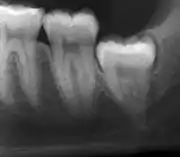

من المحتمل أن تنطمر ضروس العقل بسبب عدم التوافق بين حجم الأسنان وحجم الفك. تصنف ضروس العقل تبعًا لاتجاه انطمارها، وعمقها مقارنة بسطح العض للأسنان المجاورة وكمية تاج السن الذي يمتد خلال أنسجة اللثة أو العظم. يمكن أيضا تصنيف ضروس العقل تبعًا لوجود أو عدم وجود الأعراض والمرض. غالباً ما يبدأ فحص وجود ضروس العقل في أواخر مرحلة المراهقة عندما قد تصبح الأسنان المتطورة جزئياً منطمرة.يشمل الفحص عادة الفحص السريري بالإضافة إلى الأشعة السينية مثل أشعة البانوراما.

إذا لم يتم تقييم السن من خلال الفحص السريري وحده، يتم التشخيص باستخدام صورة شعاعية بانورامية أوCBCT. ضروس العقل التي لم تبزغ لا يزال لديها احتمالية البزوغ، يتم استخدام العديد من عوامل التخمين لتحديد فرصة انطمار ضرس العقل. نسبة المسافة بين طول تاج الضرس والمساحة المتاحة، وزاوية الضروس مقارنةً بالضروس الأخرى هما الأكثراستخدامًا في التخمين حيث تكون نسبة المساحة هي الأكثر دقة. على الرغم من القدرة على الحركة إلى مرحلة البلوغ المبكر، يمكن توقع احتمالية إصابة السن عندما تقل نسبة المساحة المتاحة لطول تاج السن عن 1.[3]:141